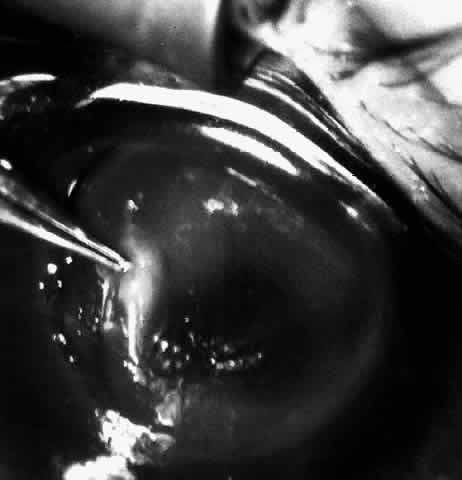

Children who have traumatic cataracts with corneal lacerations are well served by this procedure because the injury often destroys the capsular support that can be used to stabilize an intraocular lens.16–18 The epikeratophakia graft provides structural support for the weakened cornea and minimizes the induced irregular and regular astigmatism, in addition to correcting the optical error (Figs. 3 AND 4).

Fig. 4. Same patient as in Figure 11, with epikeratophakia lenticule in place 3 months after surgery. (Morgan KS, Ellis GS, Marvelli TL, Arffa RC: Epikeratophakia in children. with traumatic cataracts. J Pediatr Ophthalmol Strabismus 23:108–113, 1986)